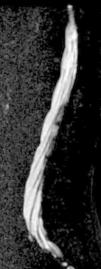

Estudio completo de la columnaLa técnica de la RM permite valorar toda la columna, aunque su adquisición debe realizarse de forma independiente entre los segmentos cervical, dorsal o lumbar. Con los avances tecnológicos es posible realizar una reconstrucción de posprocesado de los distintos segmentos adquiridos en el estudio para que puedan valorarse en una única imagen global de toda la columna. La posibilidad de evaluar toda la columna permite identificar lesiones en distintas zonas que pueden modificar el diagnóstico o el manejo terapéutico del paciente, especialmente en caso de enfermedad degenerativa, traumática7, tumoral (fig. 3) o de origen inflamatorio. La técnica de estudio completo de la columna se realiza de forma habitual en la valoración de la RM de cuerpo entero que se describe a continuación.